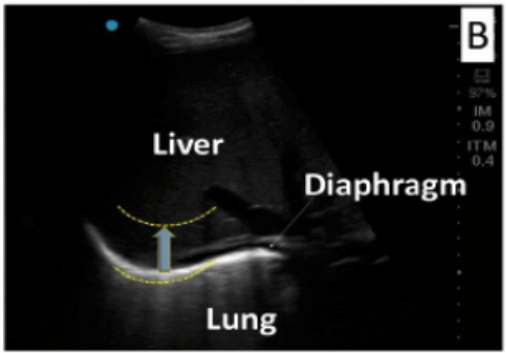

膈肌作为人体最主要的吸气肌,其运动和相关解剖学参数可以通过床边超声来获得。一般在肋下区和肋间区这两个声窗位置进行探查。在肋下区,膈肌被视为一个深弯曲的结构,分隔胸部和腹部;在腋窝中部肋间区,膈肌为三层结构:腹膜由两个高回声的外膜(腹膜和胸膜)包围的低回声的内层肌肉层。因此,在膈肌吸气收缩时,超声可观察到:①肋下区域膈肌吸气尾侧位移(偏移);②在肋间区中,呼气末肌肉厚度(静止时)和吸气时膈肌增厚和变硬。

(1)肋下区

肋下区二维视图显示膈肌为一条白色高回声曲线(黄色描线),分隔肺和肝

图片

肋下区M型超声显示短暂断开呼吸支持后正常呼吸时的偏移

偏移量测量